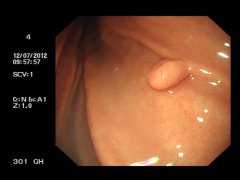

什么是胃息肉? 胃息肉(gastric polyp)是指胃黏膜局限性良性隆起病變。息肉這一名稱不表示它的病因及組織學(xué)構(gòu)造,只表示肉眼觀察到的隆起物。 胃息肉的病因: 目前病因不明。胃息肉是指起源...

胃息肉是指胃黏膜局限性良性隆起性病變,一般無臨床表現(xiàn)。部分患者可以出現(xiàn)上腹部不適、隱痛、燒心、反酸、惡心、不思飲食、慢性腹瀉等。胃息肉的病理分型有炎癥性息肉、增生性息肉和...